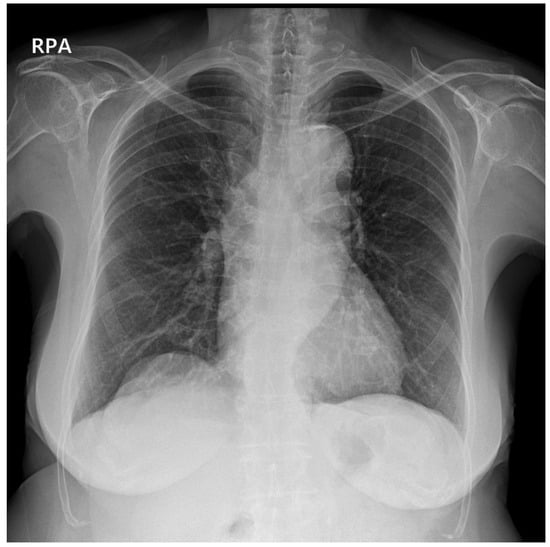

2. Case Description